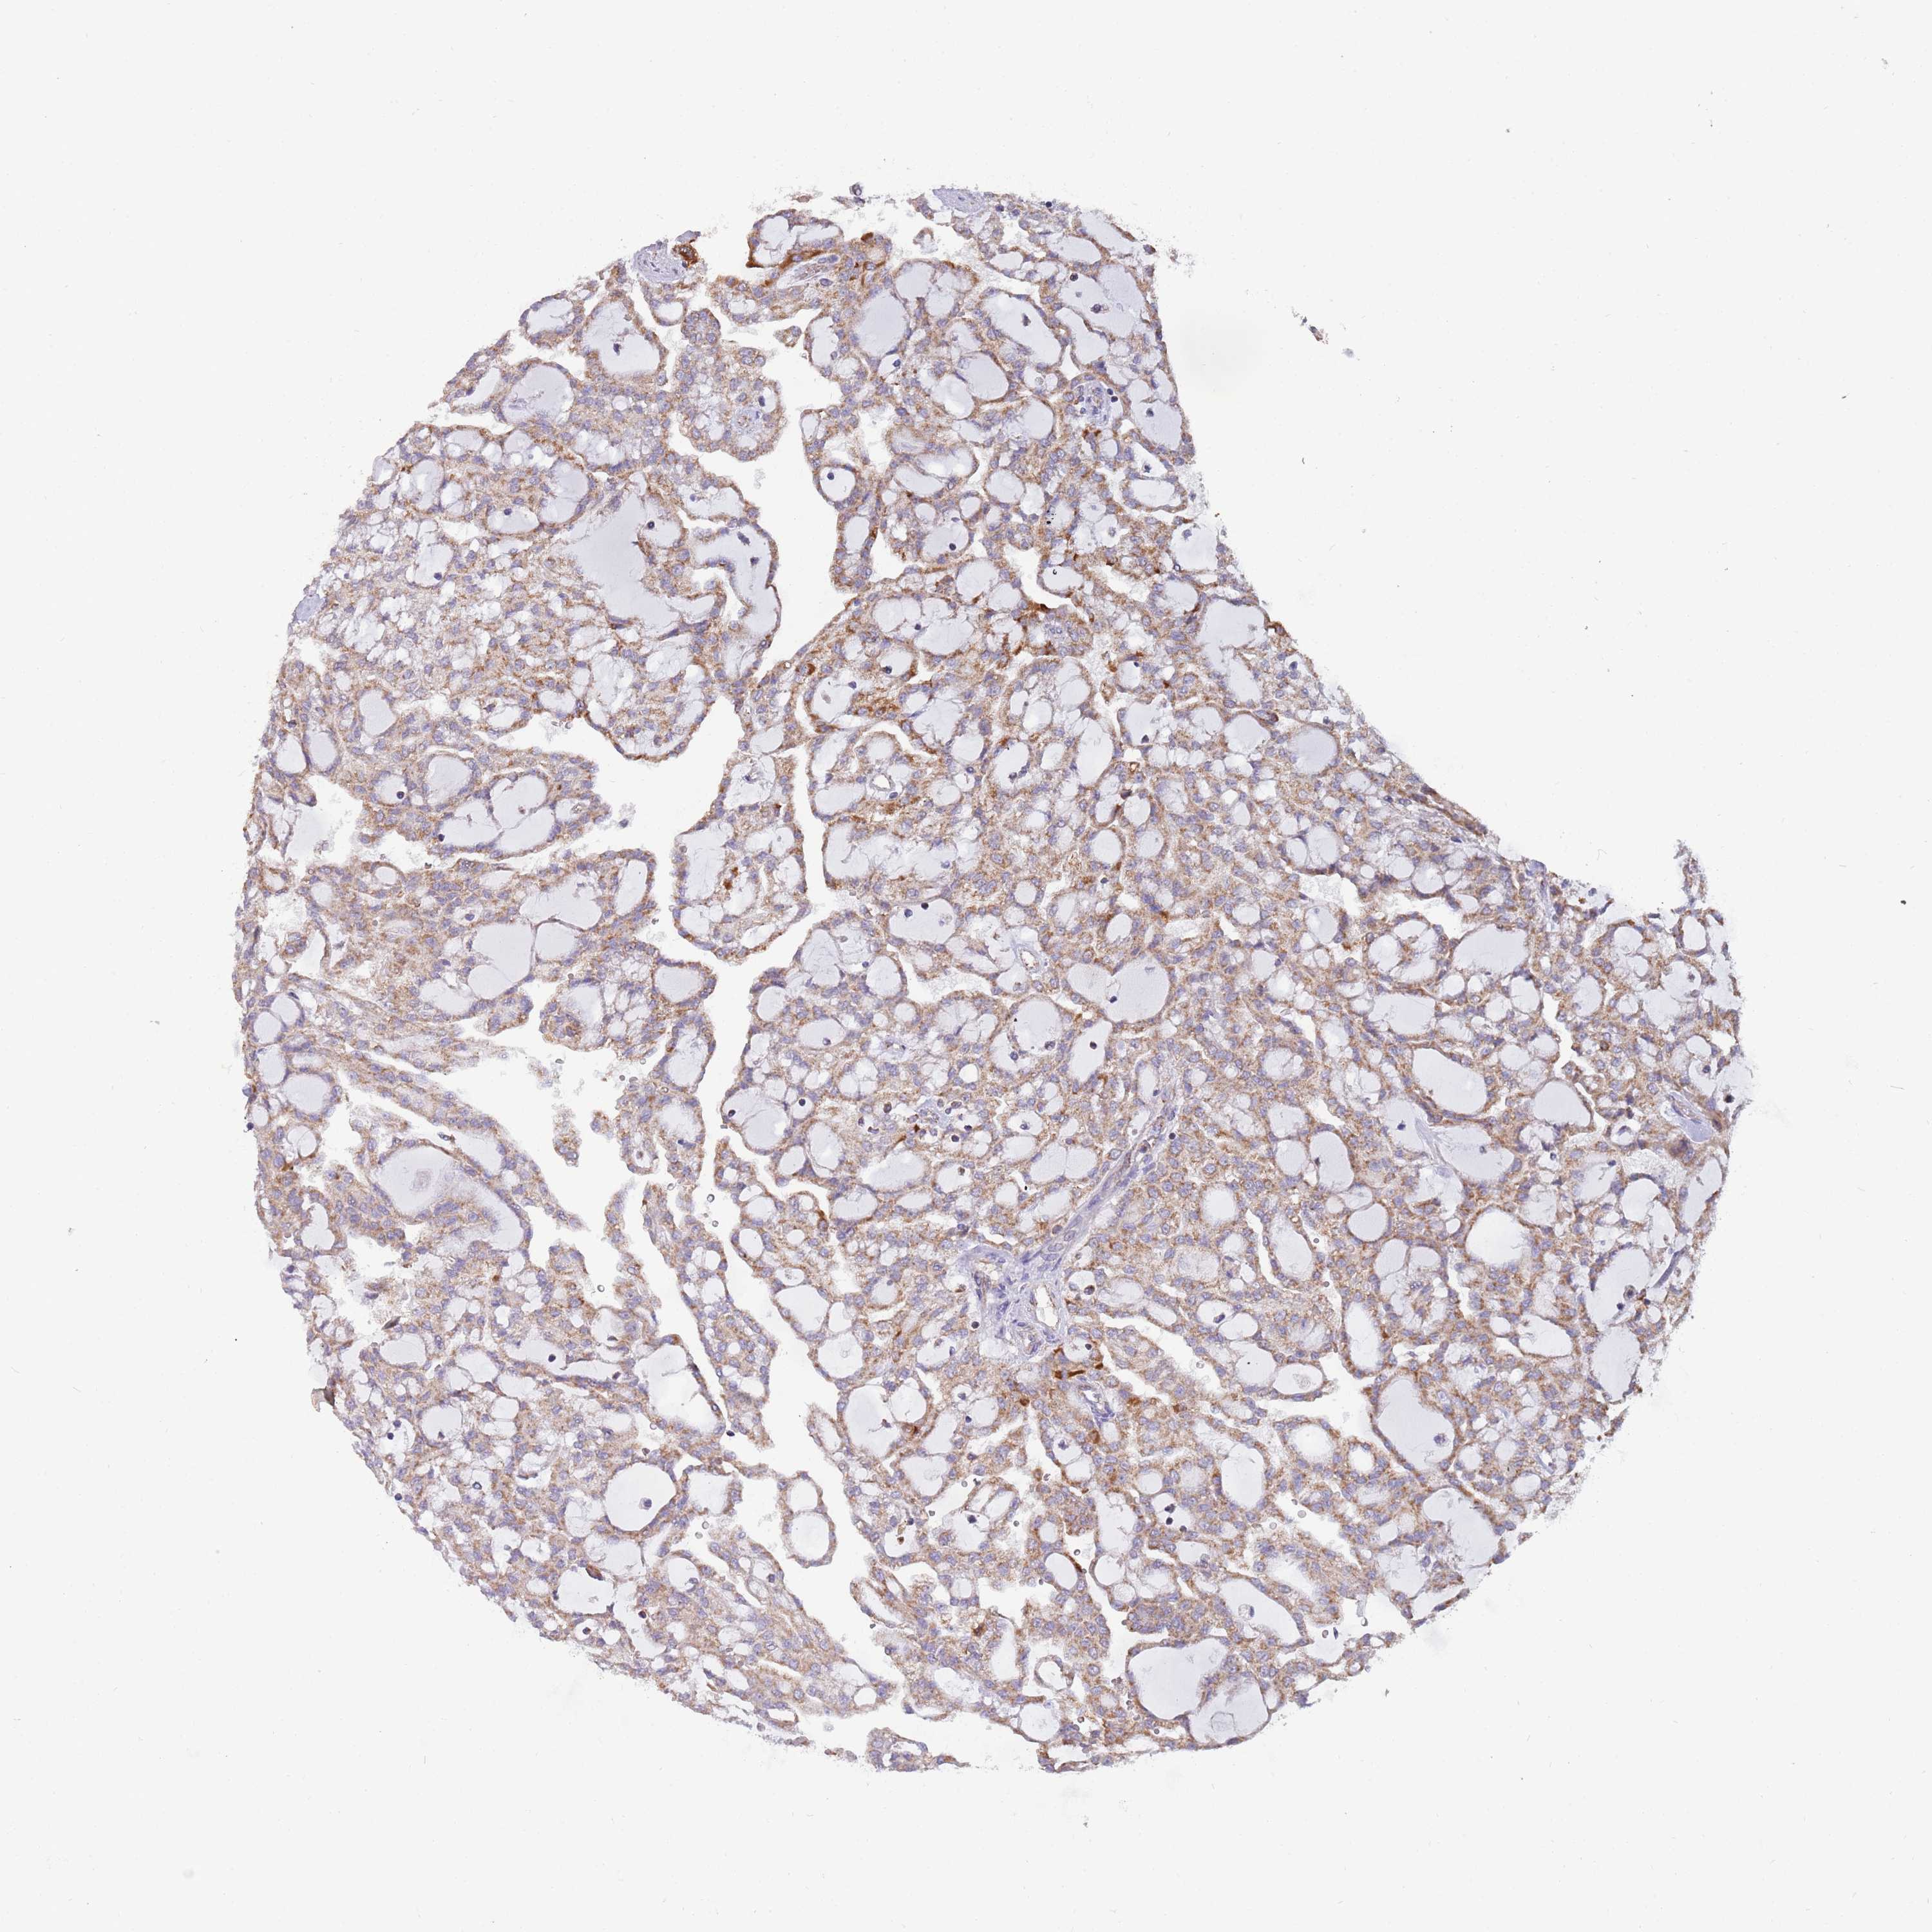

KIDNEY RENAL CLEAR CELL CARCINOMA (TCGA) - Interactive survival scatter ploti

The Survival Scatter plot shows the clinical status (i.e. dead or alive) for all individuals in the patient cohort, based on the same data that underlies the corresponding Kaplan-Meier plots. Patients that are alive at last time for follow-up are shown in blue and patients who have died during the study are shown in red.

The x-axis shows the expression levels (FPKM) of the investigated gene in the tumor tissue at the time of diagnosis. The y-axis shows the follow-up time after diagnosis (years). Both axes are complimented with kernel density curves demonstrating the data density over the axes. The top density plot shows the expression levels (FPKM) distribution among dead (red) and alive patients (blue). The right density plot shows the data density of the survived years of dead patients with high and low expression levels respectively, stratified using the cutoff indicated by the vertical dashed line through the Survival Scatter plot. This cutoff is automatically defined based on the FPKM cutoff that minimizes the p-score. The cutoff can be changed by dragging the vertical line or by entering a cutoff value in the square labeled "Current cut-off".

Under the Survival Scatter plot the p-score landscape (black curve; left axis) is shown together with dead median separation (red curve; right axis). Dead median separation is the difference in median mRNA expression between patients who have died with high and low expression, respectively. It is calculated as follows: median FPKM expression of dead patients with high expression - median FPKM expression of dead patients with low expression. This is intended to aid the user in visually exploring custom cutoffs and the associated p-scores and dead median separation.

Individual patient data is displayed and can be filtered by clicking on one or more of the category buttons on the top of the page. Categories describing expression level and patient information include: high, low, alive, dead, female, male and tumor stages. The scale of the x-axis can be toggled between linear and log-scale by clicking on the "x log" button. Mouse-over function shows TCGA ID, patient information and mRNA expression (FPKM) for each patient.

& Survival analysisi

Kaplan-Meier plots summarize results from analysis of correlation between mRNA expression level and patient survival. Patients were divided based on level of expression into one of the two groups "low" (under cut off) or "high" (over cut off). X-axis shows time for survival (years) and y-axis shows the probability of survival, where 1.0 corresponds to 100 percent.

VPS16 is not prognostic in Kidney Renal Clear Cell Carcinoma (TCGA)

Best expression cut offi

Based on the FPKM value of each gene, patients were classified into two groups and association between prognosis (survival) and gene expression (FPKM) was examined. The best expression cut-off refers the FPKM value that yields maximal difference with regard to survival between the two groups at the lowest log-rank P-value. Best expression cut-off was selected based on survival analysis .

When clicking on this number, the vertical dashed line indicating cut-off, the interactive survival plot, and the Kaplan-Meier curve will be adjusted to show results based on the best expression cut-off.

: 20.04

Median expressioni

Median expression refers to the median FPKM value calculated based on the gene expression (FPKM) data from all patients in this dataset. When clicking on this number, the vertical dashed line indicating cut-off, the interactive survival plot, and the Kaplan-Meier curve will be adjusted to show results based on the median expression.

: N/A

Median follow up timei

Median follow up time refers to the median time (years) after diagnosis with this type of cancer, based on clinical data from all patients in this dataset.

P scorei

Log-rank P value for Kaplan-Meier plot showing results from analysis of correlation between mRNA expression level and patient survival.

N/A

5-year survival highi

5-year survival for patients with higher expression than the expression cutoff.

For melanoma and glioma, 3-year survival is shown.

5-year survival lowi

5-year survival for patients with lower expression than the expression cutoff.

TCGA RNA samplesi

RNA-seq data is reported as average FPKM (number Fragments Per Kilobase of exon per Million reads), generated by the The Cancer Genome Atlas (TCGA) .

Normal distribution across the dataset is visualized with box plots, shown as median and 25th and 75th percentiles. Points are displayed as outliers if they are above or below 1.5 times the interquartile range. FPKM values of the individual samples are presented next to the box plot.

Average pTPM 17.9

Number of samples 521